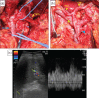

A 71-year-old woman presented to our hospital because pancreatic head cancer was suspected on a medical checkup. Computed tomography showed a 30 mm low-density lesion in the pancreatic head, and the stenosis of the celiac axis (CA) due to the median arcuate ligament (MAL) compression. We made a preoperative diagnosis of pancreatic head cancer and performed laparotomy. Transection of the MAL failed to restore adequate hepatic arterial flow, necessitating arterial revascularization, which was achieved by end-to-end anastomosis between the gastroduodenal artery and the middle colic artery. After reconstruction, Doppler ultrasonography showed improved hepatic arterial signal. The patient was discharged 16 days after surgery with no complications. When planning pancreaticoduodenectomy (PD) for such patients with CA stenosis due to MAL compression, surgeons should simulate a situation of insufficient hepatic arterial flow after division of the MAL, and prepare for reconstruction of the hepatic artery during PD.